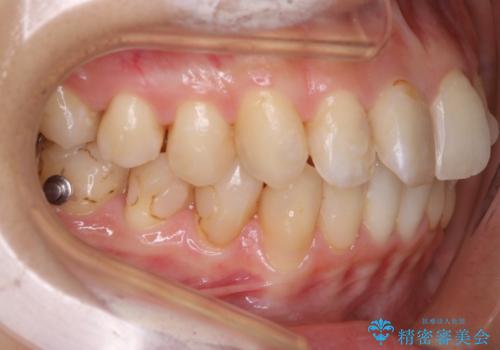

歯のガタつきをとるためのスペース作りの方法の一つにディスキング(IPR)という方法があります。

歯と歯の間を一ケ所あたり最大0.5mmまでの範囲内で削ることで歯自体が少し小さくなり、それにより作られるスペースを数ヶ所分合わせることで合計で数mmの大きなスペースが作れるという方法です。

当院ではなるべく歯の機能や見た目に影響の出ないよう、作業時に拡大鏡の使用や削るタイミングの微調整を行っています。